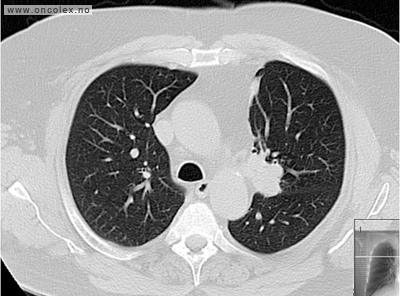

CT  med kontrast er den mest brukte røntgenundersøkelsen. Kontrastvæsken gis gjennom en kanyle (venflon) i armen. Svulster i leveren synes oftest best på MR. MR eller CT-tynntarm kan påvise nevroendokrine svulster i tynntarmen som ikke ses på vanlig MR/CT.

Bildeeksempler